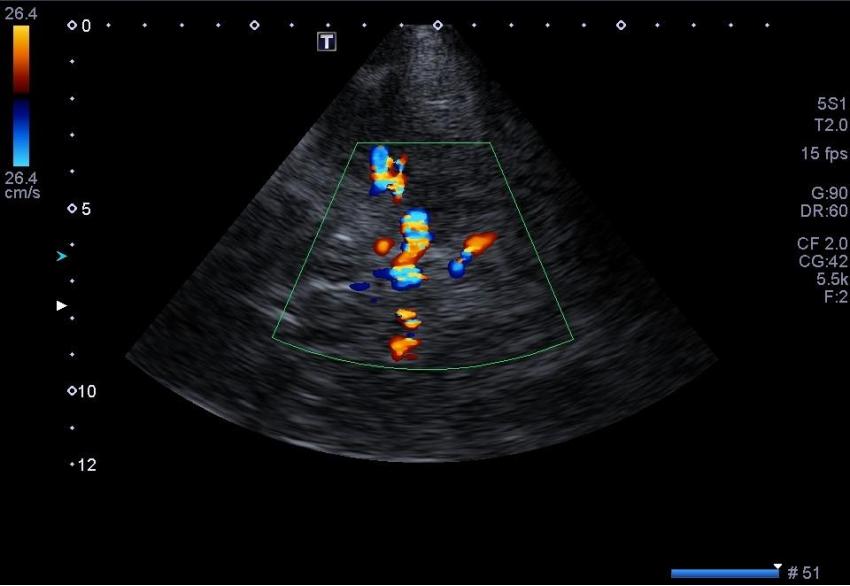

The examination is performed with a sector transducer through 'cranial windows', as these are the areas where bones of the skull are thinner and allow the best transmission of ultrasound. On the side of device, a good penetrating ability is provided by a stream of waves with low frequency. Since the higher the frequency, the faster the ultrasound wave attenuates, it is best to use transducers with a frequency of 1-6 MHz.

However, in order to obtain a diagnostically-appropriate image, one sensor with the appropriate frequency is not enough. You also need a machine with a good power which allows us to obtain an image with acceptable 2D resolution and high color Doppler sensitivity. We all know that machines are divided into different classes. In this article, we want to show you that for a good head vascular examination, it is not necessary to choose a premium class machine with an exorbitant price.

If we want to consider devices of the class below expert, but above average, we can safely choose between Siemens NX2/Siemens NX3 or Acuson X700, Toshiba Xario 100/ Xario 200